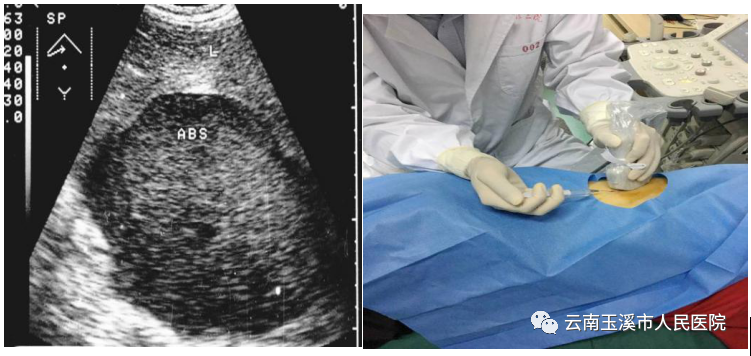

1.选择穿刺点:在B超引导下,确定体表与脓腔之间能避开腹腔内其他脏器的直接径路。

2.在穿刺点做局部麻醉后,可先用细针穿刺,吸出脓液后(图1.10.2.1-1),将标本送培养及镜检,然后更换14号粗穿刺针尽量抽净脓液,并用生理盐水反复冲洗,再注入抗生素(图1.10.2.1-2)。